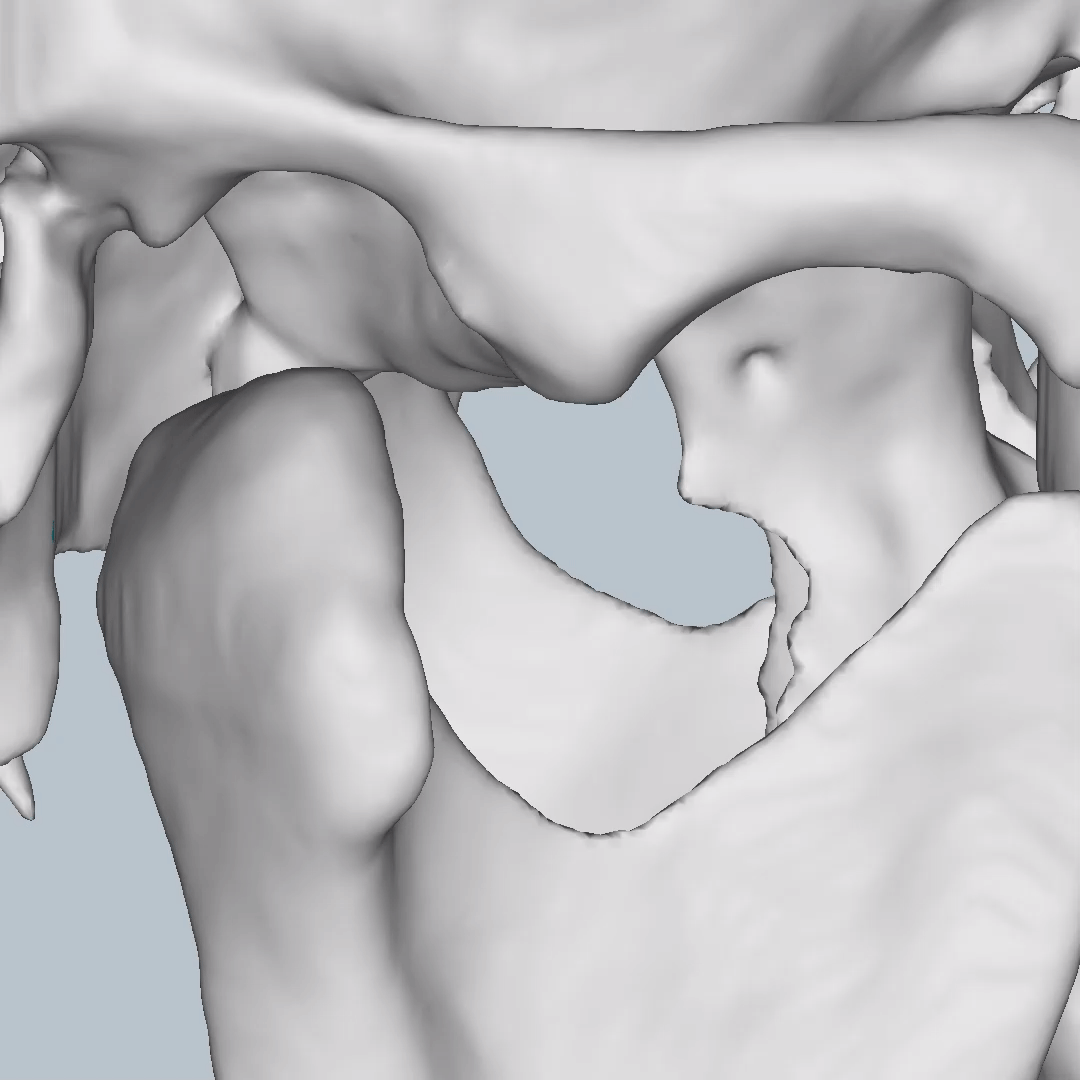

So what is Segmentation? It basically means taking the CBCT and delineating all the different 3D structures, bones, individual teeth, etc.

These can then be individually exported via the software by generating STL files from CBCT dicom data. This can be used in other dental software. Jaw STLs can be used in Modjaw (jaw motion capture) for TMJ analysis, for example. As well as in exocad to help visualize the jaws for surgical planning or guide creation.

- CBCT segmentation

STLs of upper and lower jaws imported into Modjaw for TMJ analysis in jaw motion. this is made possible by CBCT segmentation using Diagnocat.

The surgical crown lengthening guide was made with the aid of maxilla STL to visualize crestal bone level. Again thanks to CBCT segmentation by Diagnocat.